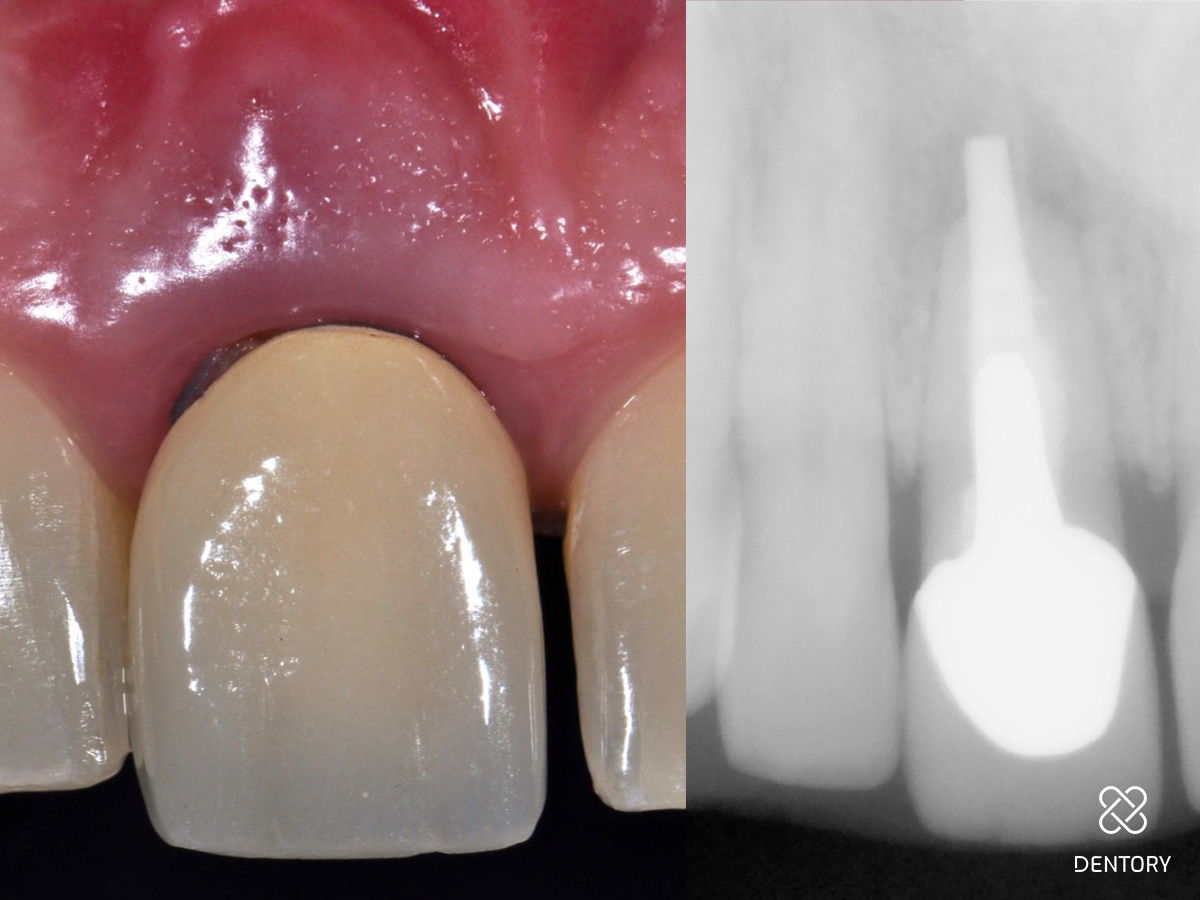

Abbildung 2

Der überkronte Zahn 11 ist elongiert und zeigt deutliche Entzündungszeichen mit einer vestibulären Schwellung.

Abbildung 3

Auf der Röntgenaufnahme ist eine apikale Entzündung im Sinne einer periapikalen Parodontitis zu erkennen.